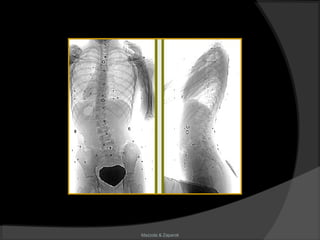

Escoliose

Mazzola & Zaparoli

Definição

“É uma deformidade ântero-posterior em

lordose, causada por um movimento em

torção de todo segmento raquidiano. Essa

deformidade se expressa lateralmente e

trata-se de uma curva reversa.”

(Perdriolle)

Aspectos radiológicos

 Topografia;

 Ângulo de Cobb;

 Rotação:

Nash-Moe

Perdriolle

 Bending – test;